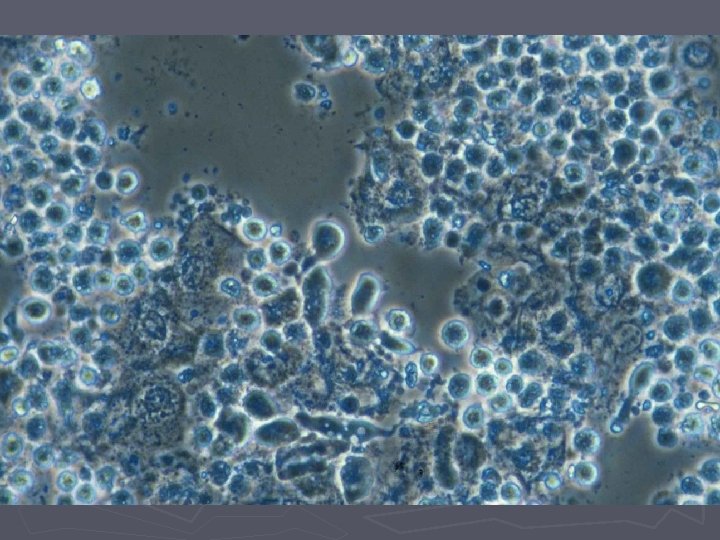

Candida ► Næsthyppigste vaginale infektion ► 80% er Candida albicans ► Asymptomatiske tilfælde ses (vaginose) ► Oftest dog gener med kløe og svie (vaginitis) ► Ved mikroskopi ses sporer og hyfer (KOHpræparatet) ► 10% er Candida glabrata som kun danner sporer.